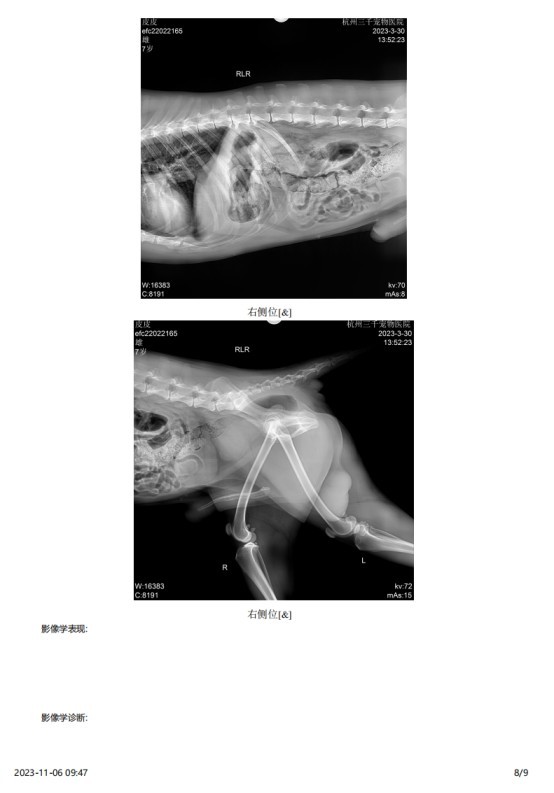

2023 年 3 月份检查结果